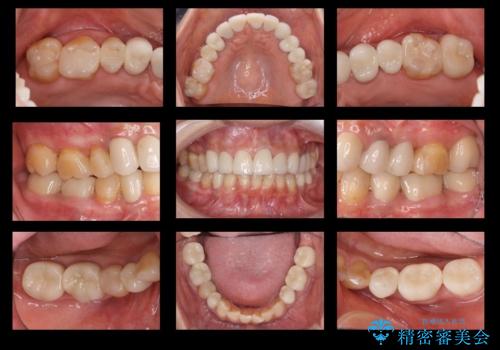

50代女性 銀歯をとって白いつめものに 全体的な治療

- 50代女性

- 銀歯や被せ物のやり替えをご希望で来院。悪いところはすべて治していきたいとのことでした。

- 356.2万円費用は治療当時の料金となります

本数も多く、時間はかかりましたが、しっかり通いきっていただきました。